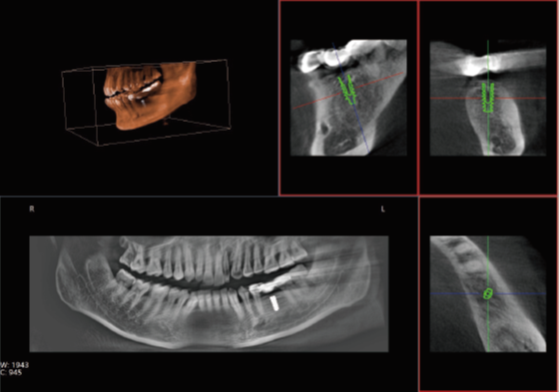

众所周知,在口腔内种植牙齿是十分精细的手术,没有先进的可视化影像设备支持的种植牙手术,就犹如盲人摸象,手术效果难以预知。口腔CT影像能测量牙槽骨的高度和宽度,估计种植部位,与下颌阻生磨牙相关的低位下牙槽神经管影响颌骨的疾病的病理学评估。

正常情况下,牙齿的排列不在一个平面上, 且具有一定的生理弧度,普通X线往往使图像相互重叠,使图片看不清楚。但是,口腔CT的三维成像对牙体、牙根、牙周膜等微细结构显示更加清晰。可以帮助医生了解断根,牙根内吸收、根管钙化、牙根结石、牙槽骨退缩等情况,能用于根管治疗前寻找根管,术后评估根管充填情况,评估牙周炎程度及预期治疗效果等。

正畸治疗前的诊断分析是治疗成功的重要步骤,口腔CT不仅能提供头颅侧位和曲断片的信息,还可以评价每个牙齿的排列位置,牙根倾斜度,牙槽骨垂直向、颊舌向的骨量,骨密度等。用于牙列不齐矫正、牙颌面畸形矫正、牙周病辅助正畸。

口腔CT与全身CT相比,具有分辨率高、X射线辐射小、投照时间短、费用低、应用广泛方便、操作简单、可以配合第三方软件获得更多信息等优点。普爱医疗口腔CT使用脉冲透视采集图像,在保证成像质量的基础上,可有效降低患者吸收的辐射剂量。实现数字化三维容积重建,冠状面、矢状面、横断面的类CT成像效果,重建全景影像,选配牙种植系统,满足牙周、牙根管、口腔矫形矫正、牙种植等临床病例提供诊断依据。